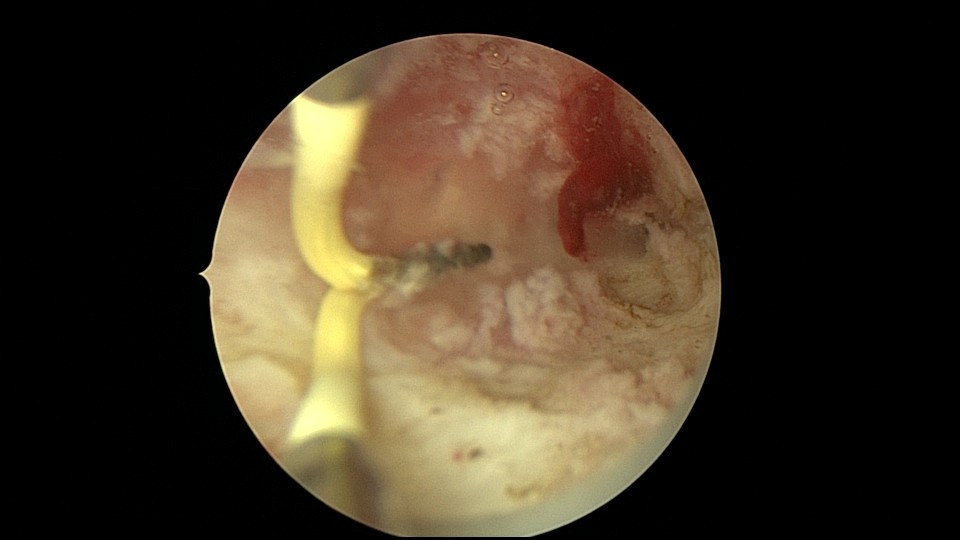

患者26岁,G7P1,剖宫产1次。2019年10月药流不全,行清宫术,术后闭经半年,后月经紊乱,周期28天~60天,月经量少。2021年4月,闭经50+天,B超提示宫腔粘连,宫腔镜见宫颈管上段封闭粘连,宫腔广泛粘连,AFS评12分(最高分)。宫腔镜电切分粘,恢复宫腔形态,显露双侧输卵管开口,宫腔防粘连复发处理,2021年5月宫腔镜二探取球囊。2021年7月自然妊娠,门诊人流并安环。2021年9月,月经推迟,B超提示宫腔粘连,节育环嵌顿,行宫腔镜取环并分粘,2021年10月二探取球囊。2021年12月放置皮埋避孕,2022年3月要求取出皮埋棒。2023年8月初自然妊娠,药流不全,2023年8月底行宫腔镜清除残留胚物。2024年2月自然妊娠10周,2024年4月初妊娠3+月(BPD2.6cm),坚决要求终止妊娠,行宫腔镜辅助终止妊娠。2025年6月因异常子宫出血再次宫腔镜分粘,2025年7月二探取球囊。现31岁,G10P1,前后共做了8次宫腔镜,术后多次自然妊娠,患者妊娠中途均选择了终止妊娠。